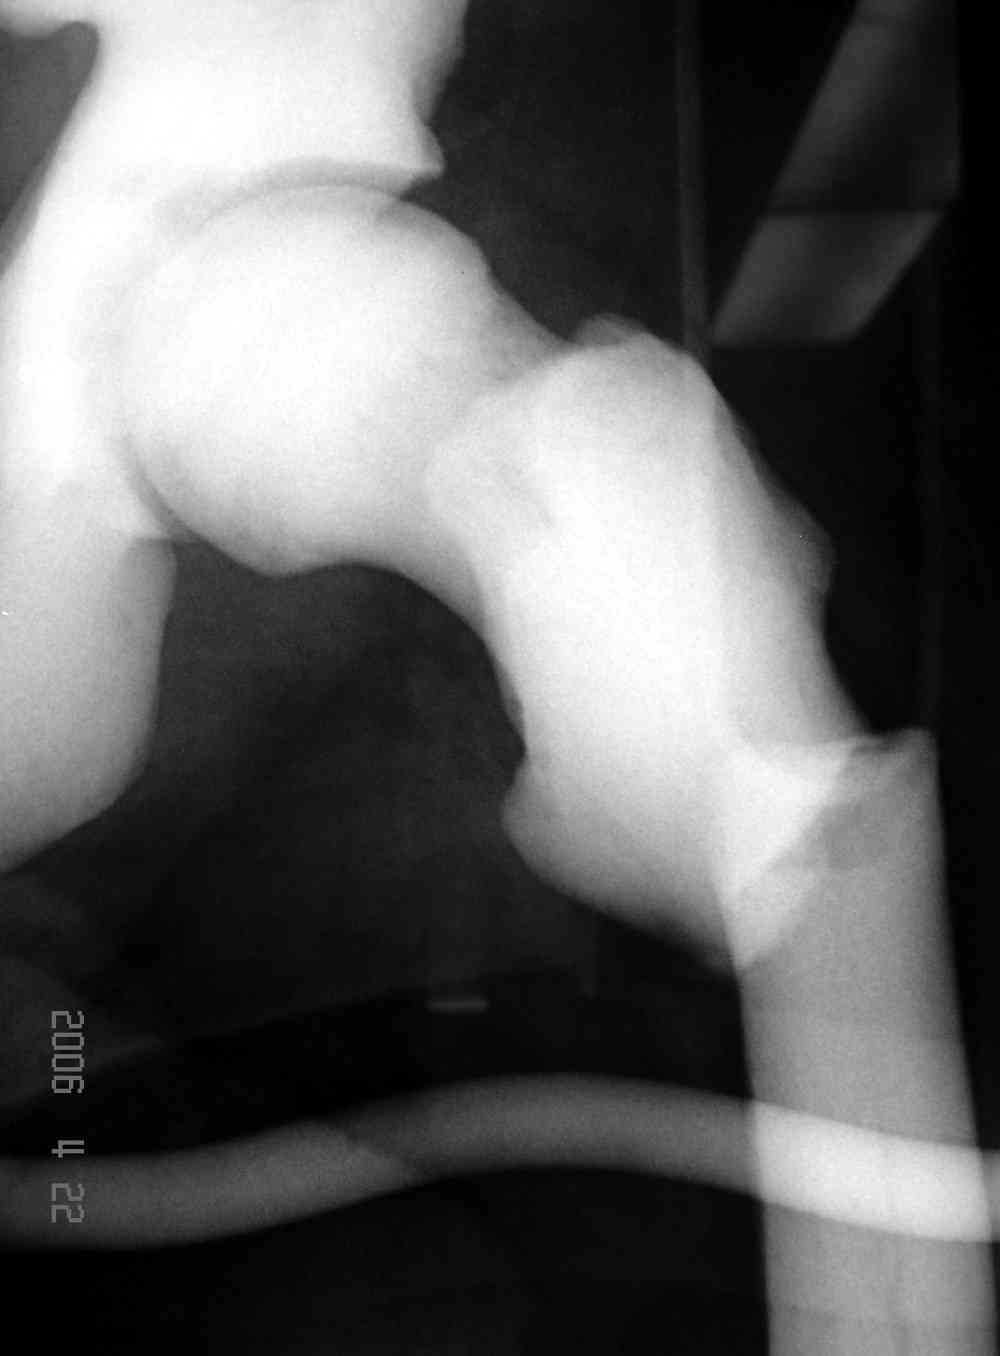

Здесь у меня дополнительные снимки с большим разрешением и в разных режимах, а то те дигитал снимки совсем очень блеклые, может, эти изображени изменят выбор тактики

После неудачной попытки скелетного вытяжения в первом мед.учреждении, после осмотра снимков и изучения истории, поставили диагноз “Остеопетроз” или мраморная болезнь, редкая наследственная костная паталогия, где имеется нарушение формации остеокластов.